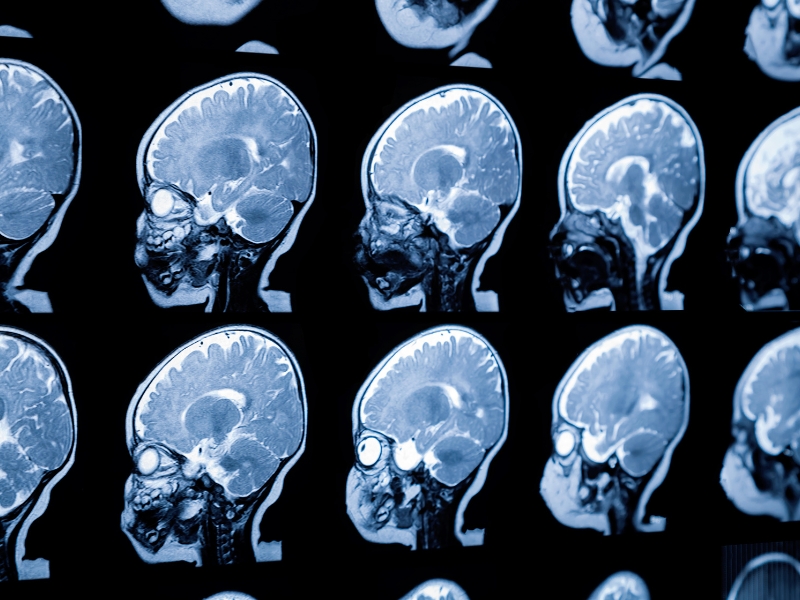

Thoái hóa chất trắng là gì?

Thoái hóa chất trắng là tình trạng tổn thương ở chất trắng, thành phần cấu tạo nên phần lớn hệ thần kinh trung ương. Chất trắng chứa các sợi thần kinh có bao myelin bao phủ, giúp tăng tốc độ và hiệu quả của việc truyền tín hiệu trong não bộ. Khi thoái hóa xảy ra, bao myelin bị hư hại, làm giảm khả năng truyền tín hiệu và gây ra nhiều vấn đề về nhận thức, vận động và cảm giác.